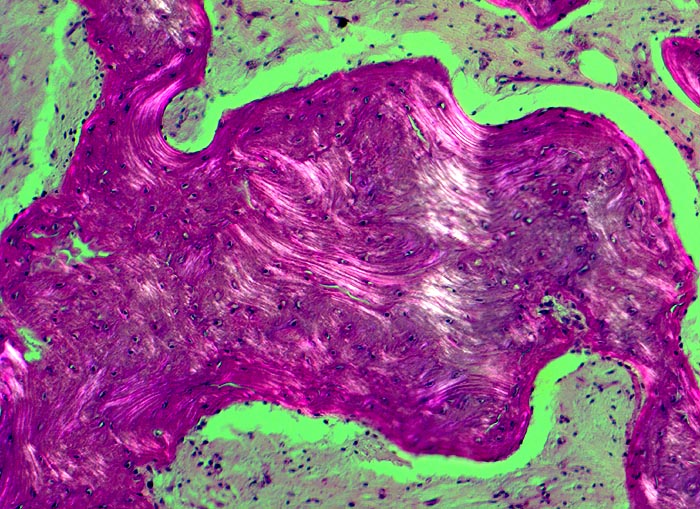

An den betroffenen Stellen ist sowohl der Knochenabbau als auch der Knochenanbau gesteigert. Die Osteoklasten sind auffallend gross und enthalten sehr viele Kerne (> 3518). Die aktivierten Osteoblasten produzieren verdickte und grob geflochtene Spongiosabälkchen. Der neugebildete Knochen ist strukturell und morphologisch abnorm und schlecht mineralisiert. Der Knochen wird dadurch weich und anfällig auf Frakturen oder Deformation unter Belastung (nach vorne gebogene Säbelscheidentibia). Das Knochenmark wird ersetzt durch fibrovaskuläres lockeres Stroma, welches an Granulationsgewebe erinnert. Mikroskopisch werden eine osteolytische Initialphase, eine Umbauphase mit verstärkter Knochenneubildung und eine sklerosierende Stabilisationsphase mit strukturellem Umbau und Spongiosierung der Kortikalis (verbreiterte spongiosaartige Kortikalis) unterschieden.

• Die Spongiosabälkchen sind auffallend verdickt, vermehrt und unregelmässig geformt.

• Prominente Zementlinien sind mosaikartig angeordnet.

• Lockere Markfibrose.